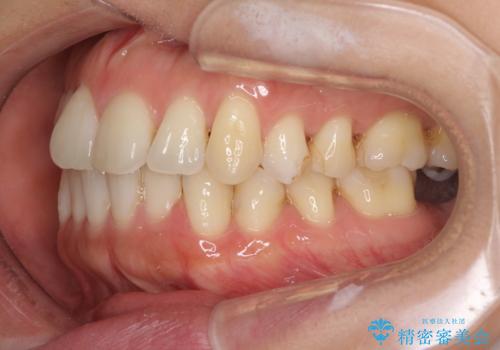

- 上下奥歯の欠損を気にして来院された患者様です。

以前矯正した後戻りにより前歯に叢生が認められたため、矯正治療の提案をしたところ、補綴治療と合わせて矯正治療を行うこととしました。

下顎欠損部はインプラントにて、上顎中間欠損部はブリッジによる補綴治療を行い、他にも気になっている銀歯をセラミックインレーやゴールドインレーにて修復治療を行うこととしました。

後戻りの程度は軽度であったため、インビザライン・ライトを用いて歯列を整えました。

再度後戻りするリスクを最小限に食い止めるため、下顎前歯の舌側を細いワイヤーで固定しました。